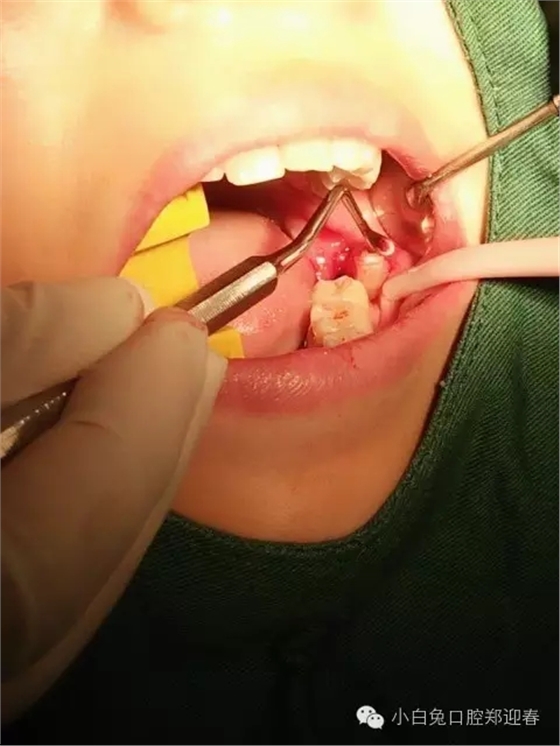

取出第一塊牙根部分,片子顯示依然存在遺留

一例智齒斷根進行二次拔除的感悟